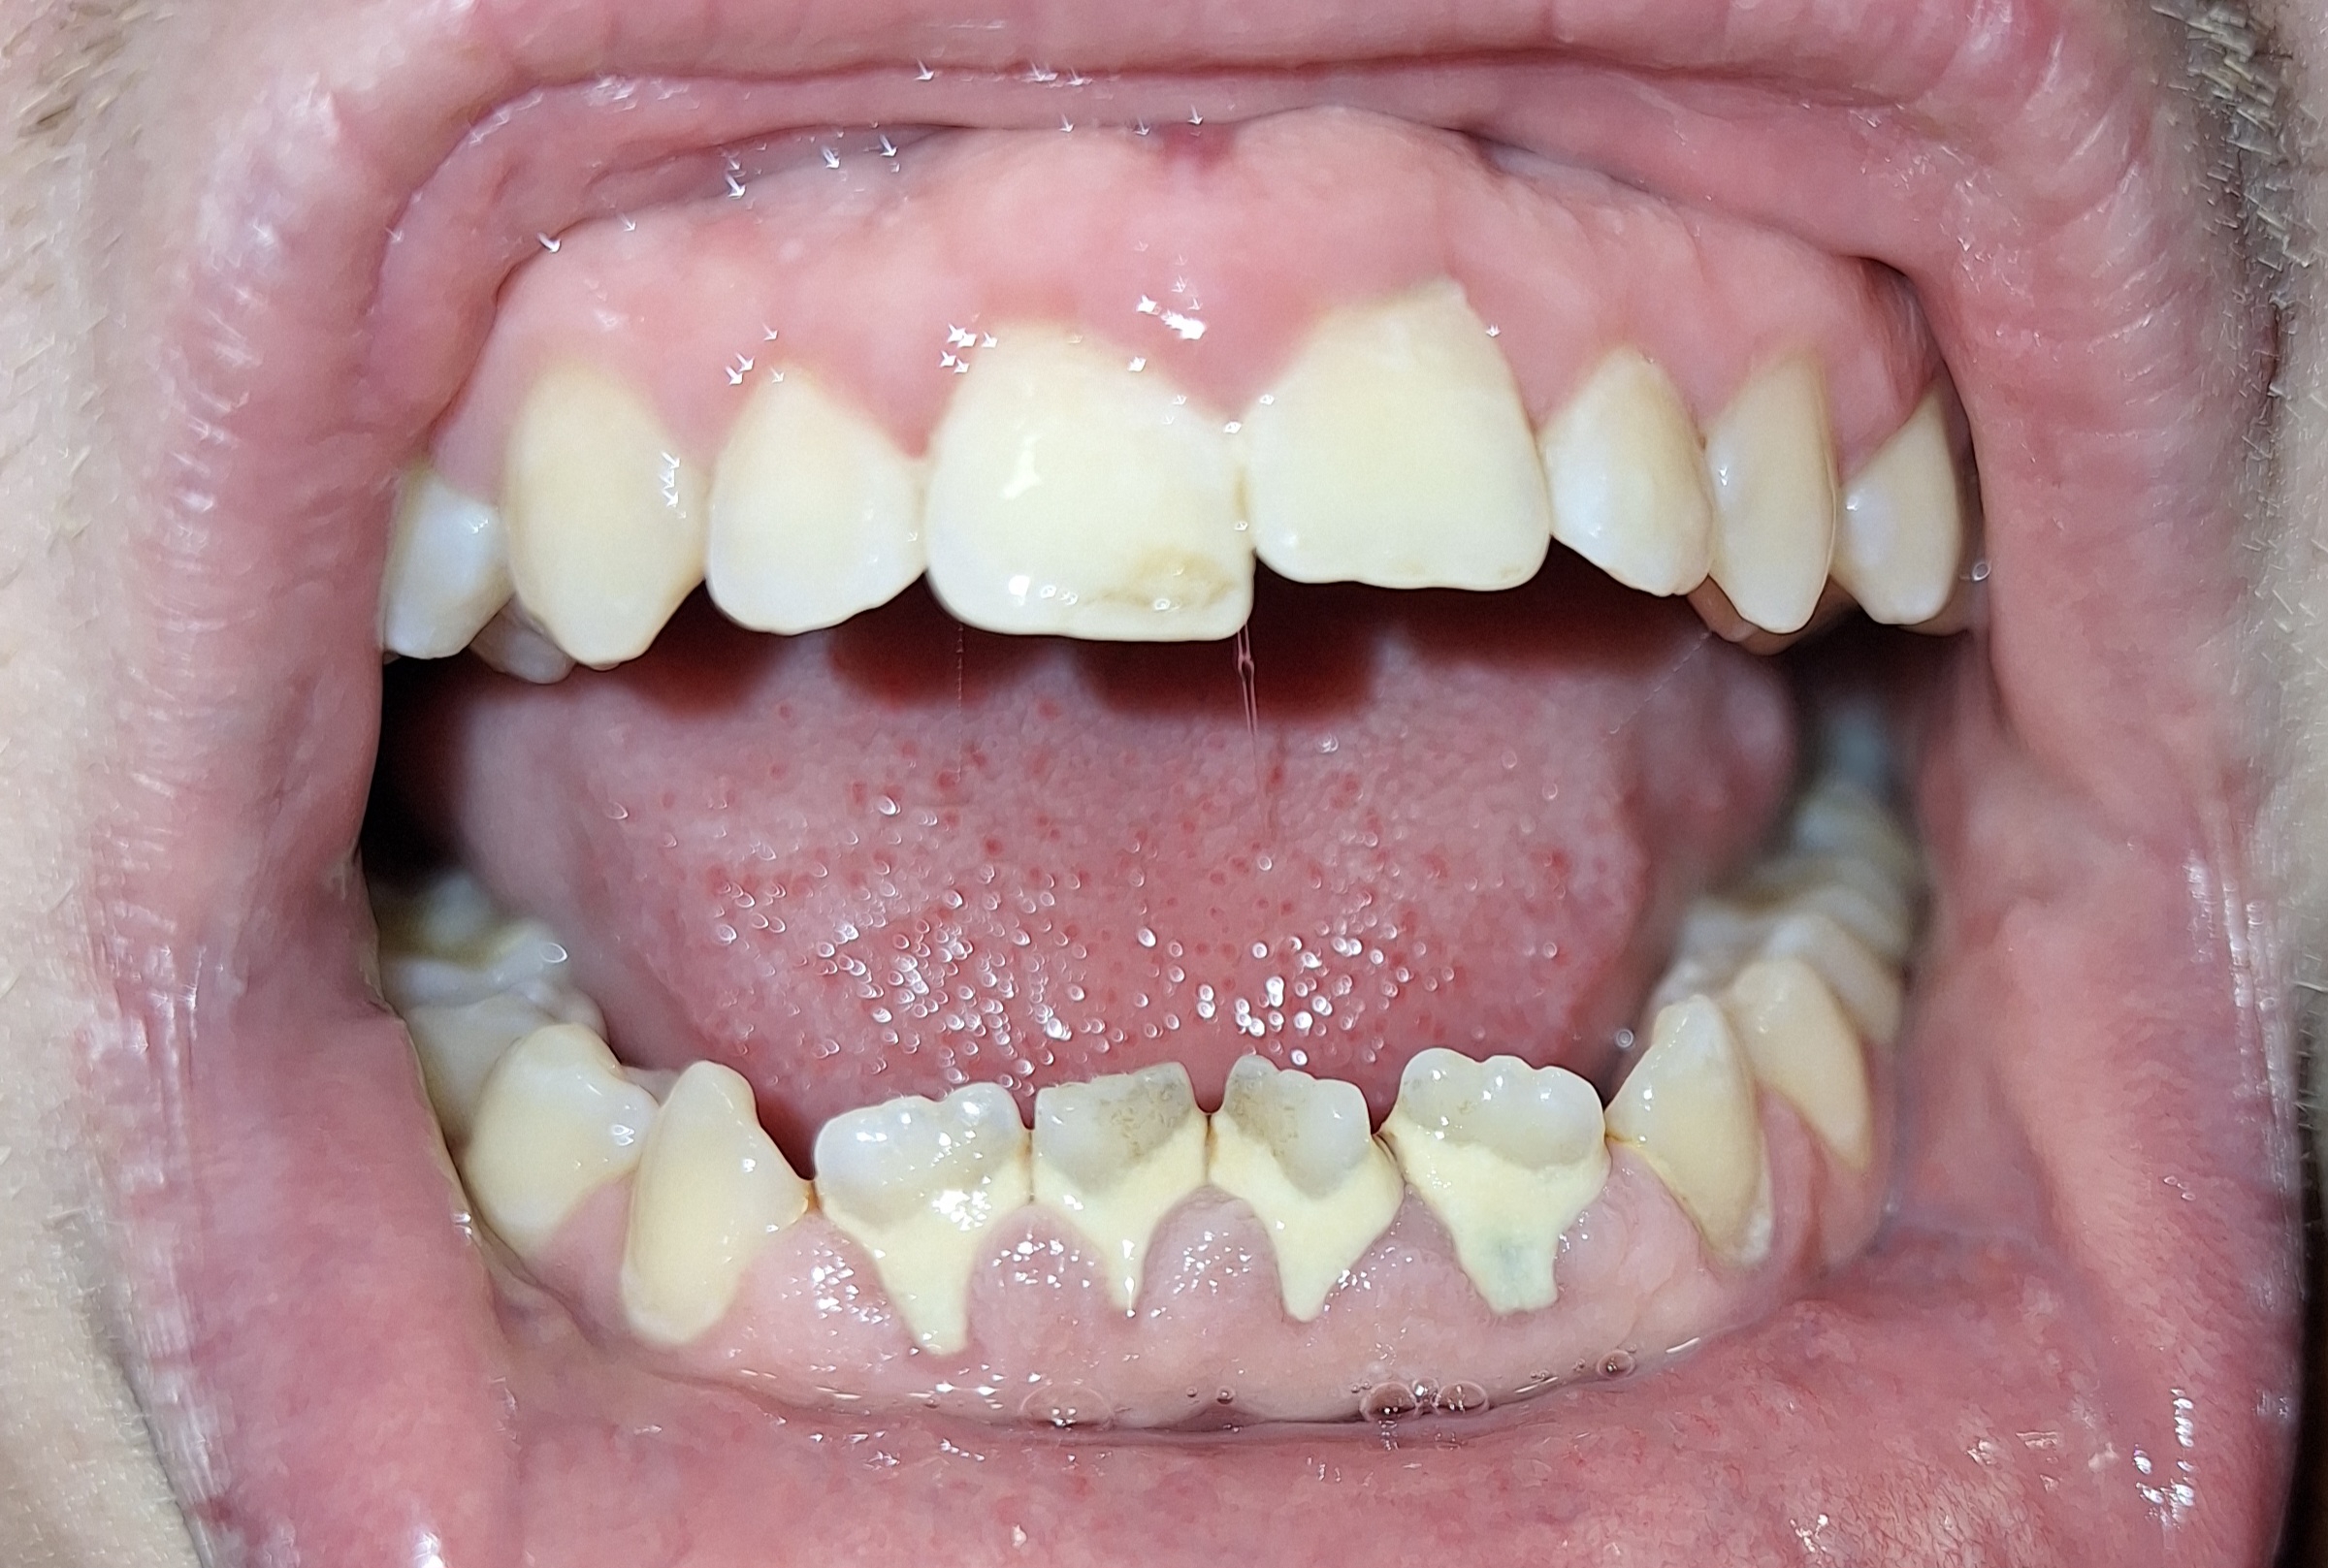

Опустились дёсны в нескольких местах, обнажились шейки зубов. Чувствительные, болят от прикосновений, могут реагировать на холодное, горячее, сладкое.

Ситуация как примерно на пик2.

В первом случае меня беспокоит, что будет, если на оголившемся участке зуба есть кариес (сейчас из-за общей более тёмной природной пигментации шеек зубов + налёта не понятно), и я зашью этот кариес под кожу? Кариес будет прогрессировать под десной?

А во втором случае, дохтур сказал, что к заделанным пломбой шейкам зубов десна уже назад не прирастёт, даже если пересадить, то есть пластика дёсен будет невозможна.